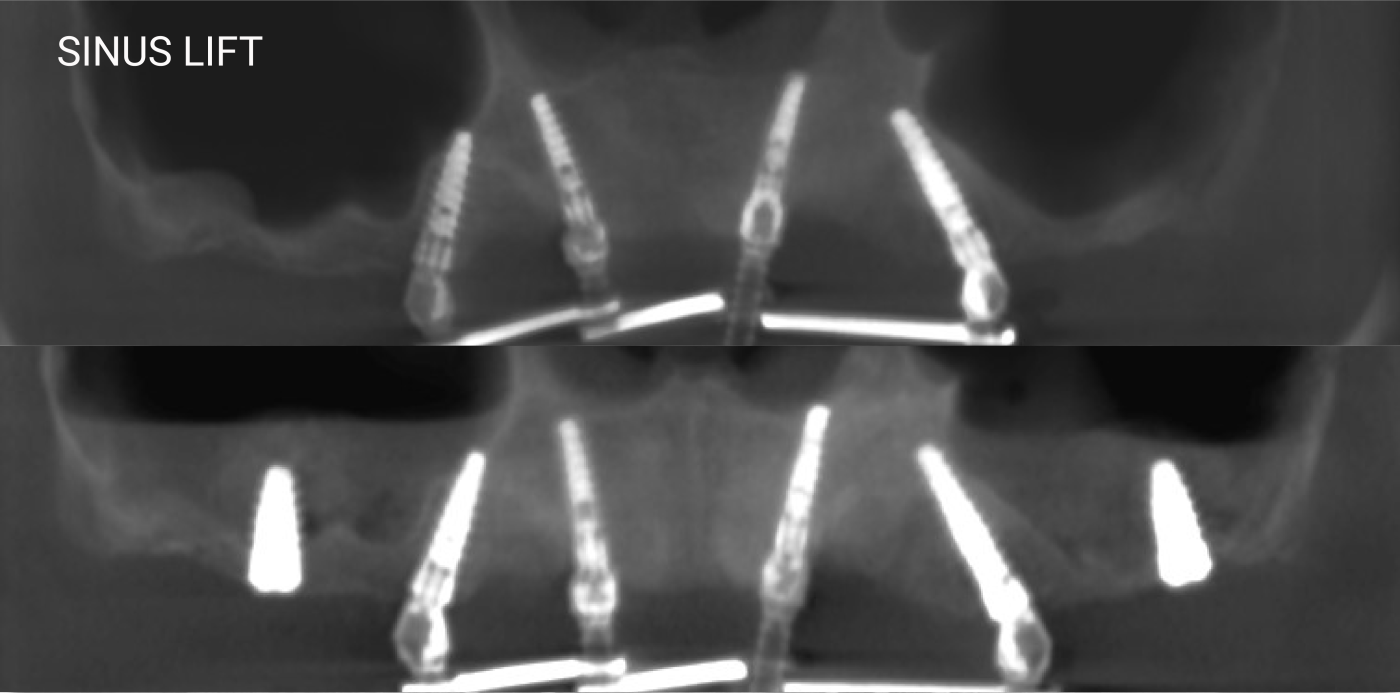

The latest Cone Beam CT Scanner: to assist our doctors in accurate diagnosis and coming up with treatment plan

Nobel Clinician software: to help our doctors determine the most suitable position for implant placement